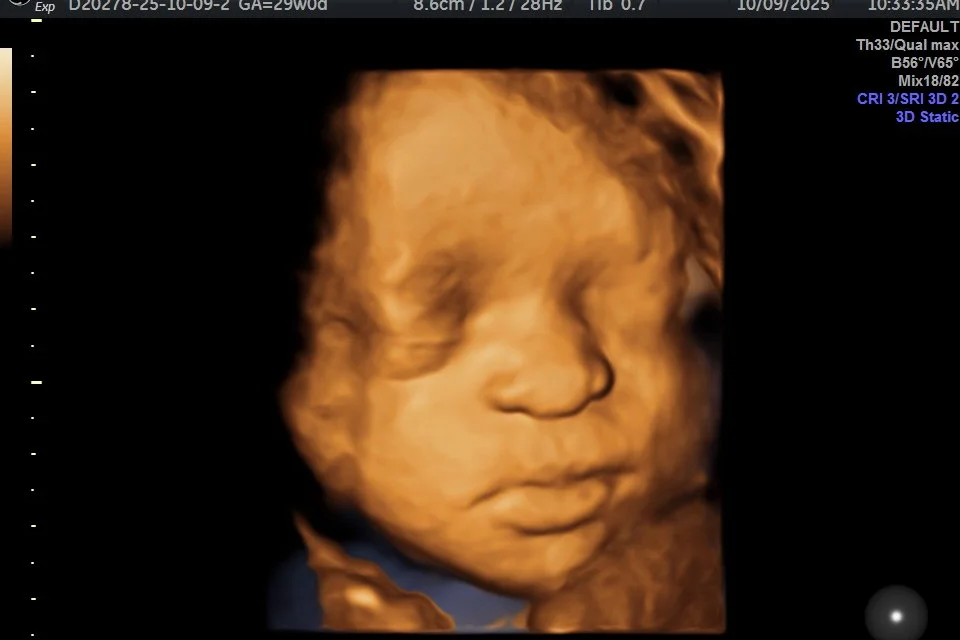

Say hello to our Baby of the Week! 🩷

Each week, we’ll pick one of our favorite ultrasound moments that totally melts our hearts.

πŸ’ž Captured at First Glimpse β€” your weekly dose of sweetness!